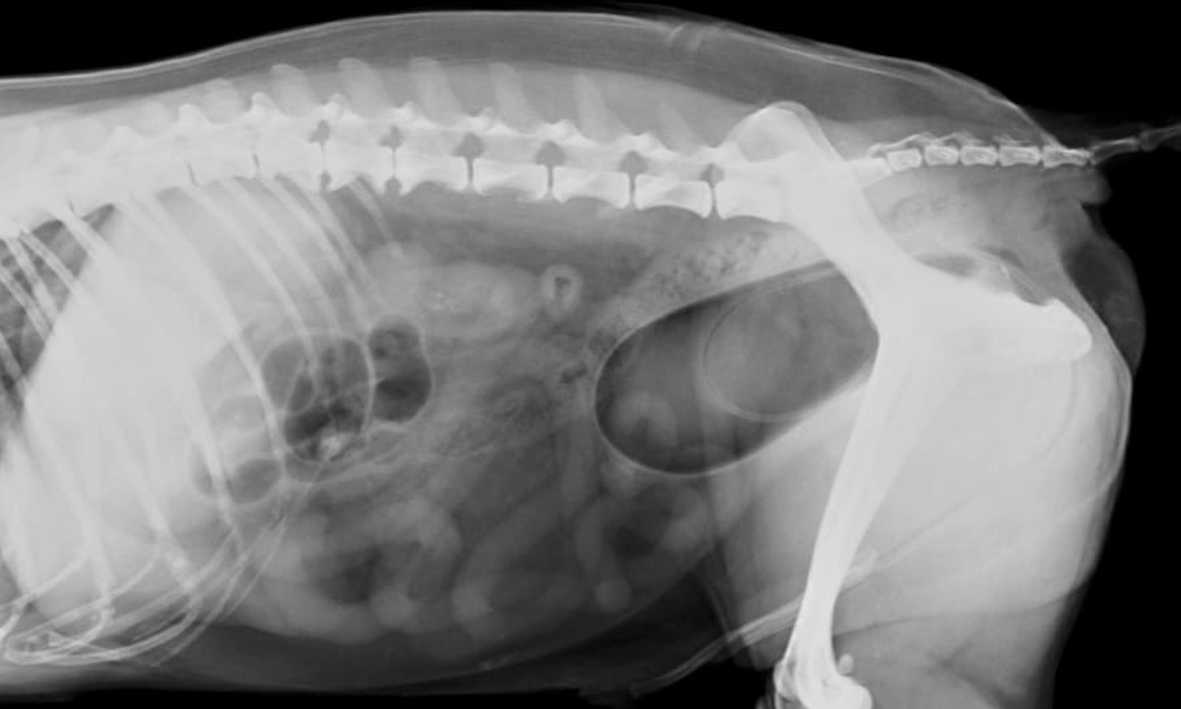

Diagnóstico por Imágenes

Radiografías Digitales, de contraste y simples, mielografías, ecografías.